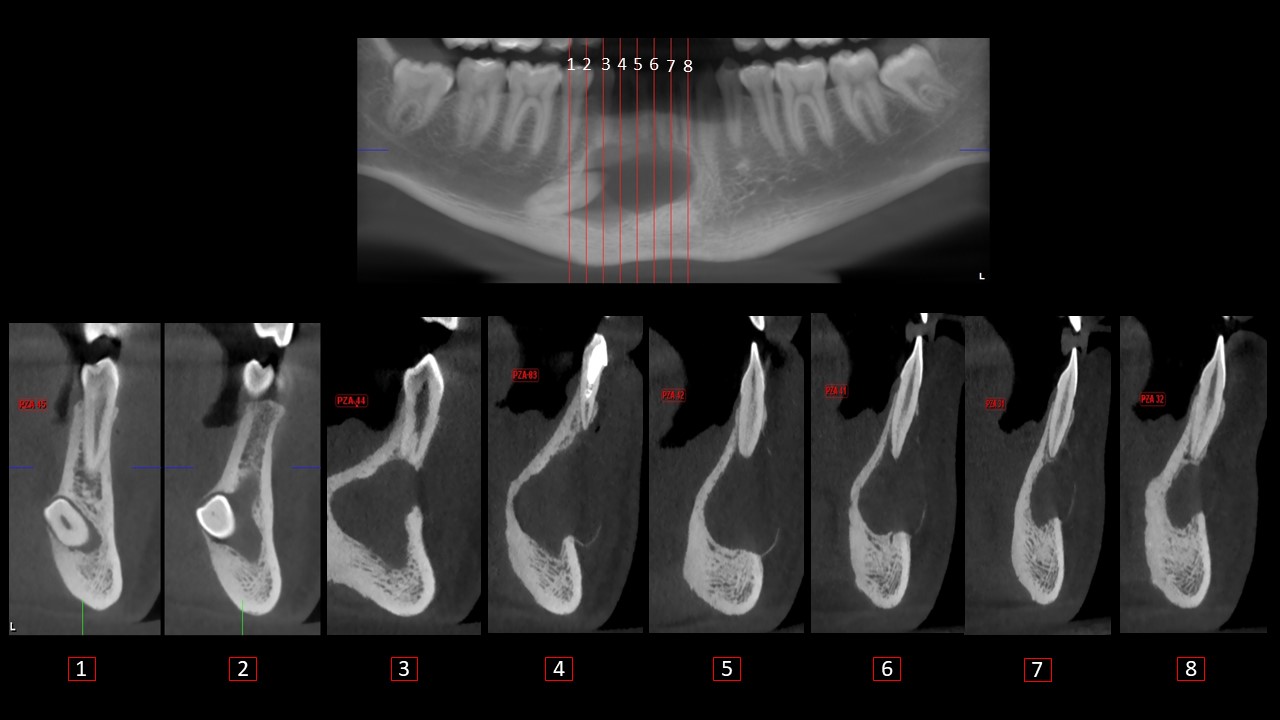

Figura 2

En los cortes axiales observamos que es una imagen isodensa pericoronaria a la pieza 43 con extensión radicular, que genera el adelgazamiento y expansión de la tabla ósea vestibular de la región sinfisiaria; además, la pieza 43 se encuentra desplazada hacia la tabla ósea lingual, generando su adelgazamiento y expansión.

En los cortes sagitales(Figura 3) y coronales(Figura 4) se evidencia que no afecta las corticales del conducto dentario inferior y presenta forma festoneada en la región anterior